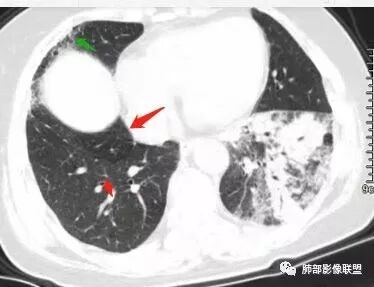

1、主病灶  左下叶斑片状、大片状致密影

这三幅图是连续的,我们看到支气管中间这一幅狭窄了

大——小——大,狭窄后扩张

从这幅图看好像与周围病灶分界不清,支气管腔狭窄后扩张,支持炎性